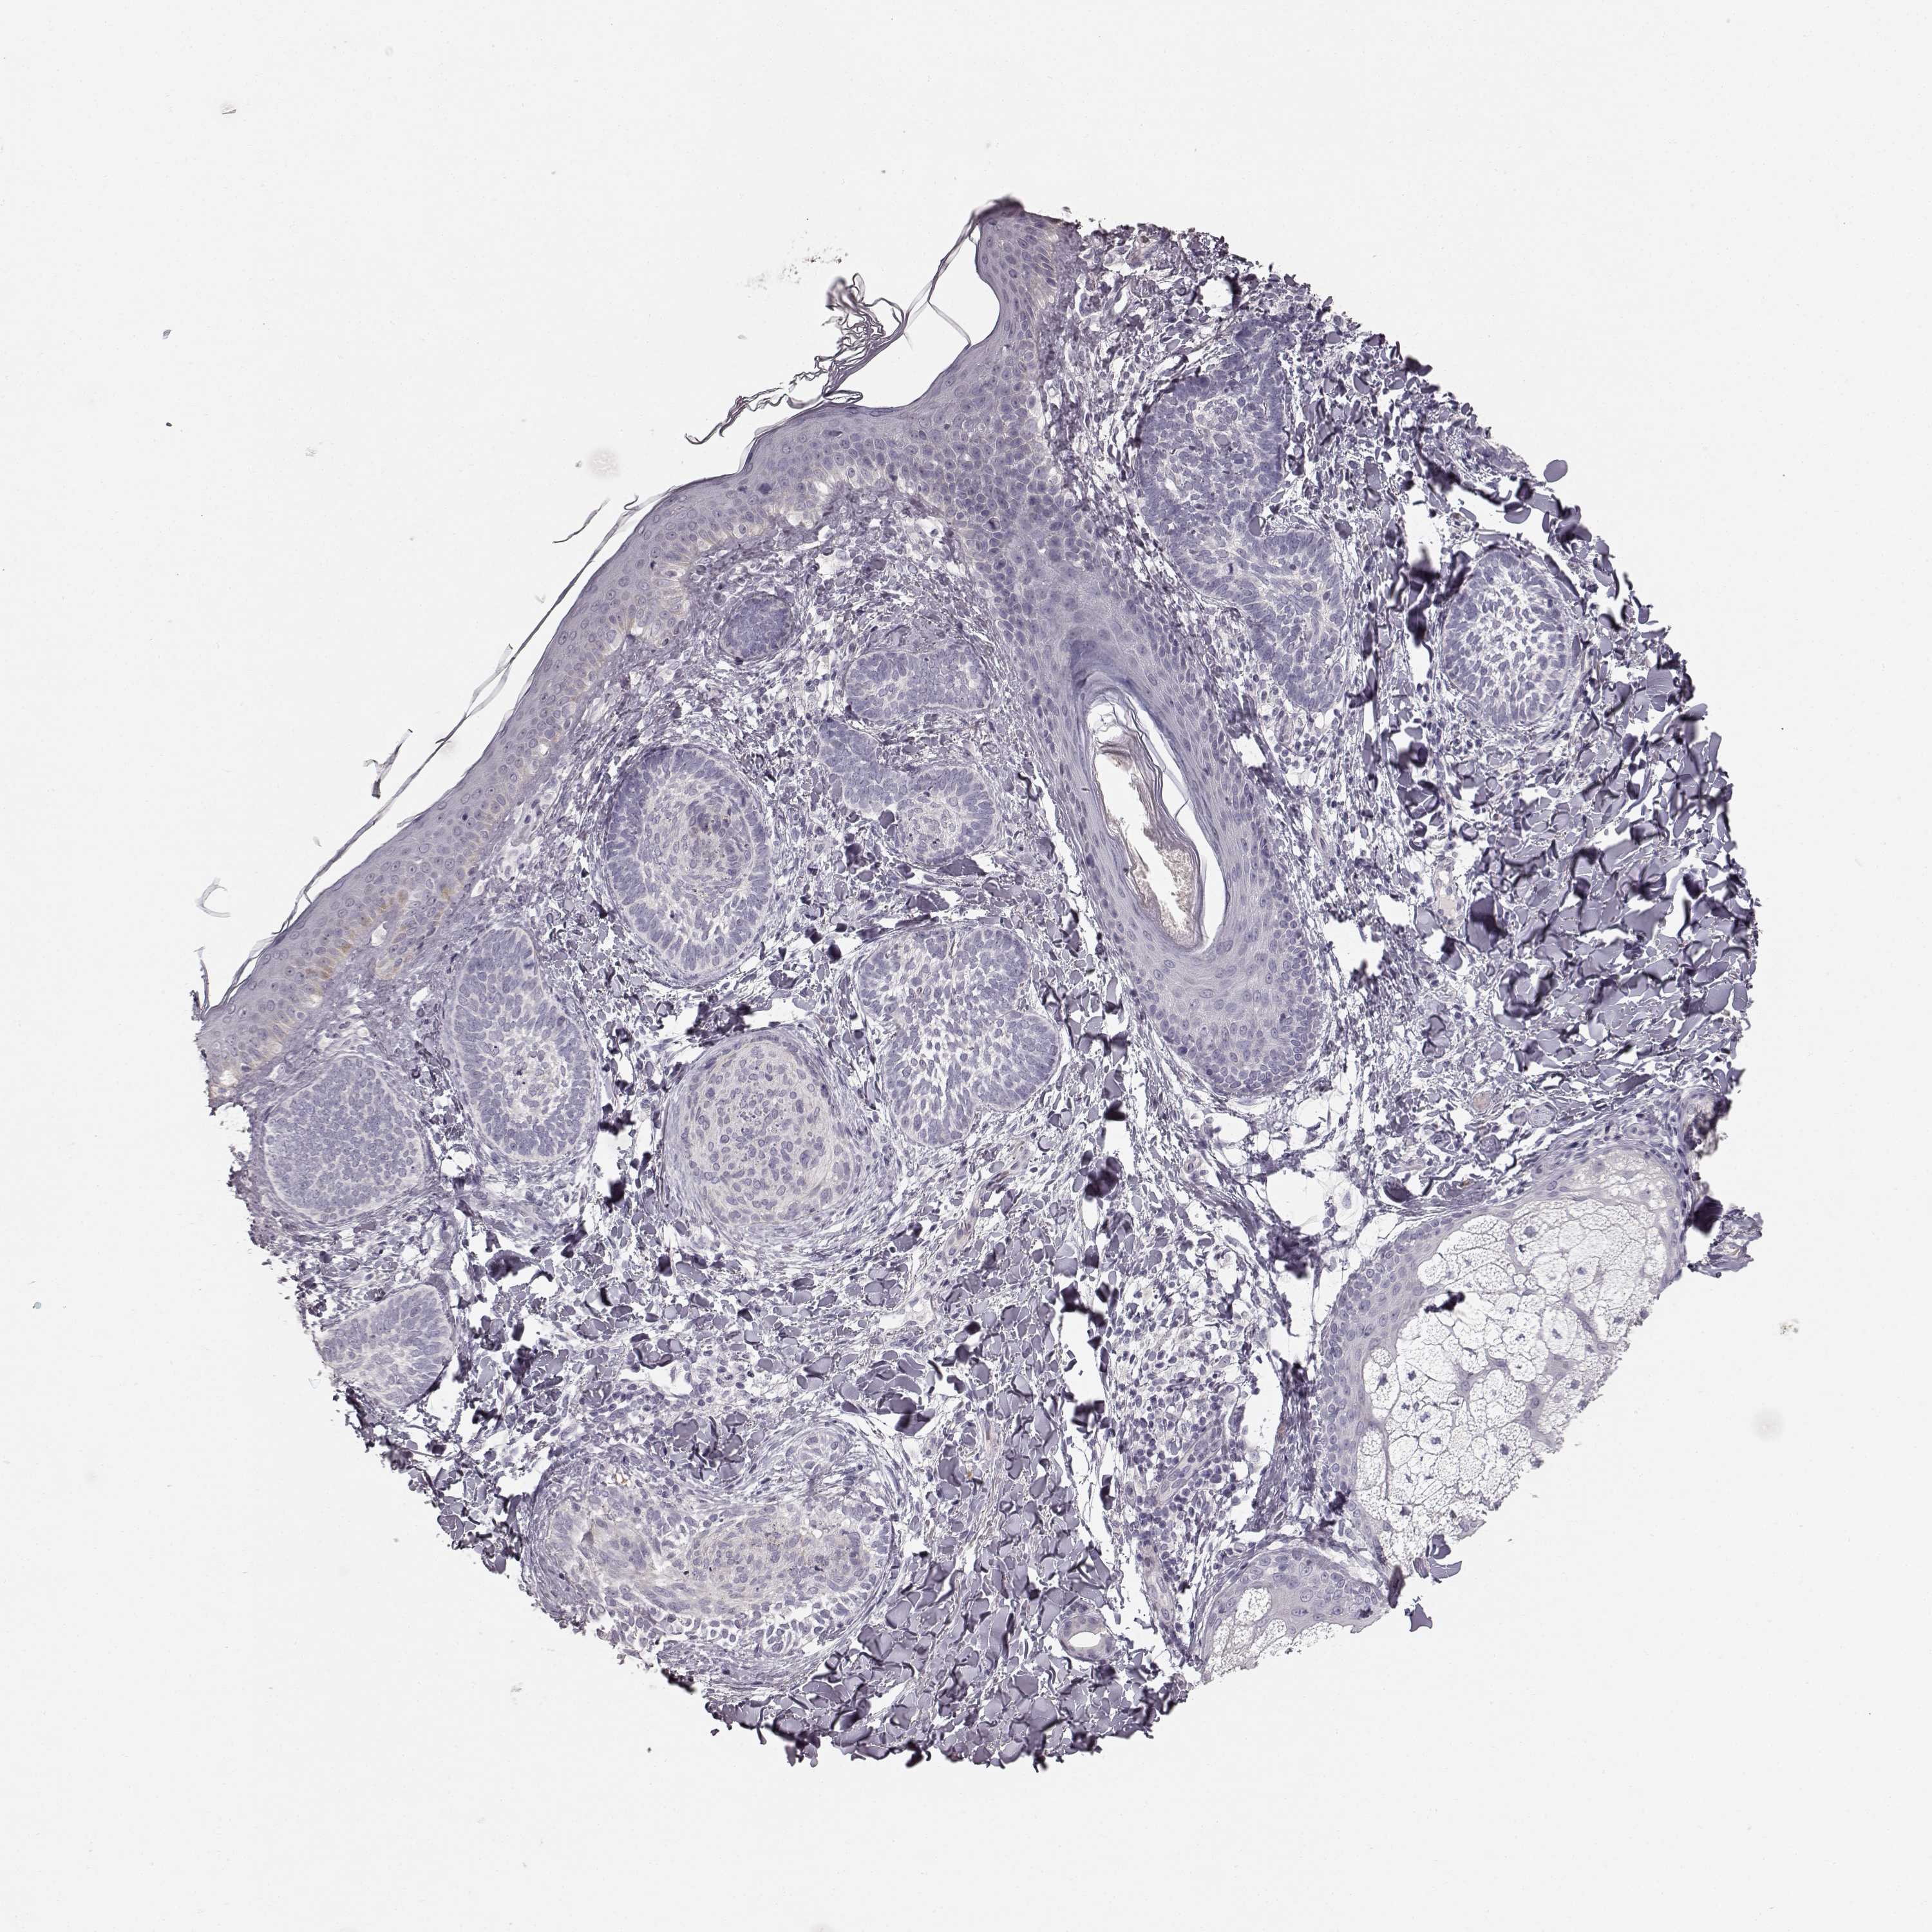

Basal cell and squamous cell cancer

SKIN CANCER - Protein expressioni

A mouse-over function shows sample information and annotation data. Click on an image to view it in a full screen mode. Samples can be filtered based on level of antibody staining by selecting one or several of the following categories: high, medium, low and not detected. The assay and annotation is described here.

Antibody stainingi

Antibody staining in the annotated cell types in the current human tissue is reported as not detected, low, medium, or high, based on conventional immunohistochemistry profiling in selected tissues. This score is based on the combination of the staining intensity and fraction of stained cells.

Each image is clickable and will lead to virtual microscopy that enables deeper exploration of all samples and also displays staining intensity scores, fraction scores and subcellular localization as well as patient and tissue information for each sample.

Antibody HPA039361

Basal cell carcinoma

Squamous cell carcinoma, NOS